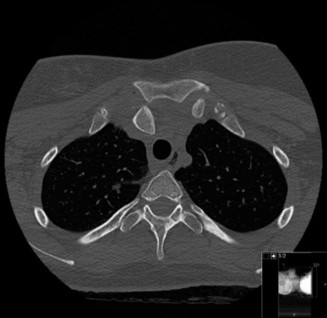

To further delineate the pathology, a CT arthrogram of the left shoulder is ordered. This is the most appropriate next step in management, as established in the primary clinical vignette. The CT arthrogram serves a dual purpose: it provides unparalleled high-resolution, three-dimensional assessment of periprosthetic bone stock and component micro-motion, while the intra-articular contrast allows for the evaluation of capsular integrity and the presence of loosening. If contrast is seen tracking between the glenoid component and the native bone bed, loosening is definitively confirmed. Furthermore, the CT arthrogram is superior to MRI in this specific scenario because standard MRI is heavily degraded by metal artifact (even with MARS protocols), making the assessment of the immediate periprosthetic interface difficult. The CT scan confirms contrast extravasation behind the glenoid component, confirming gross loosening, and demonstrates eccentric posterior wear of the polyethylene, suggesting altered joint kinematics.

Pearl: The CT arthrogram is an invaluable tool in the diagnostic workup of the painful TSA. It provides superior visualization of component micro-motion, polyethylene wear, and capsular integrity compared to standard MRI, which is heavily obscured by metal artifact. Contrast extravasation at the implant-bone interface is pathognomonic for loosening.

Clinical & Radiographic Imaging Archive